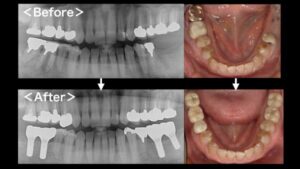

インプラントとは、顎の骨にチタン製のインプラント(人工歯根)を植立し、それを土台に上から人工歯を被せることで、歯の欠損を補う治療方法のことです。当クリニックではオペ専用の診療室を完備し、インプラント治療に力を入れております。おかげさまで数多くの治療実績を確立し、他の歯科医院様からの委託を受けてのインプラント治療も行っております。

これまでのインプラント治療では最低でも2回の外科処置が必要で、治療期間が長期にわたるため患者様の負担が大きくなるデメリットがありました。抜歯即時埋入は治療期間を短くできるので、患者様の時間的・費用的負担を軽減できる治療法です。